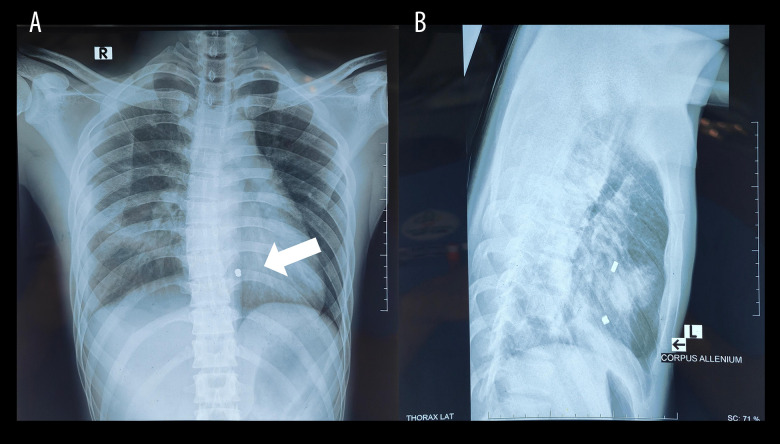

运动中经常使用的气步枪可造成复杂的、暴力性的、外伤性的心脏损伤,其发病率和死亡率都很高。与火器弹不同,气枪弹丸缺乏旋转运动,但可以达到100到230米/秒的速度。病例报告一名21岁男子在右胸气枪受伤后被转介至我院。伤后10小时出现胸痛,但血流动力学稳定。体格检查显示呼吸音减少,右半胸有压痛。胸部x线显示右侧胸血和肺挫伤,提示放置胸管,初始引流500cc出血性液体。经胸超声心动图发现右心室高回声肿块,伴轻度心包积液。计算机断层扫描证实弹丸位于右心室后部,距三尖瓣环0.8 cm处。进行紧急手术并成功取出完整的3×3×5毫米气枪弹丸。术后,患者出现短暂的强直阵挛性发作,给予咪达唑仑和异丙酚治疗。他接受预防性头孢曲松、静脉注射苯妥英、维生素B6、叶酸和口服阿司匹林、布洛芬和奥美拉唑。患者术后第3天病情好转,第4天出院。每周随访及出院后1个月脑电图显示正常。在2个月的随访中,患者仍无症状。结论:意识到心脏穿透伤、子弹轨迹和临床体征,以及多学科方法和患者家庭参与,对于良好的预后和长期随访至关重要。

BACKGROUND Air rifles, frequently used in sports, can cause complex, violent, and traumatic cardiac injury associated with significant morbidity and mortality. Unlike firearm projectiles, air rifle pellets lack rotational movement but can achieve velocities of 100 to 230 m/s. CASE REPORT A 21-year-old man was referred to our hospital after sustaining an air rifle injury to the right chest. He presented 10 h after injury with chest pain but was hemodynamically stable. Physical examination revealed decreased breath sounds and tenderness in the right hemithorax. Chest X-ray showed right-sided hemothorax and pulmonary contusion, prompting chest tube placement, with initial drainage of 500 cc hemorrhagic fluid. Transthoracic echocardiography identified a hyperechoic mass in the right ventricle, with mild pericardial effusion. Computed tomography confirmed the projectile was lodged in the posterior right ventricle, 0.8 cm from the tricuspid annulus. Emergency surgery was performed and successfully extracted an intact 3×3×5 mm air gun pellet. Postoperatively, the patient experienced a brief tonic-clonic seizure, which was managed with midazolam and propofol. He received prophylactic ceftriaxone, intravenous phenytoin, vitamin B6, and folic acid and oral aspirin, ibuprofen, and omeprazole. The patient showed improvement by postoperative day 3 and was discharged on day 4. Weekly follow-ups and an EEG 1 month after discharge showed normal results. At the 2-month follow-up, the patient remained asymptomatic. CONCLUSIONS Awareness of cardiac penetrating wounds, bullet trajectory, and clinical signs, along with a multidisciplinary approach and patient-family involvement, is crucial for favorable outcomes and long-term follow-up.